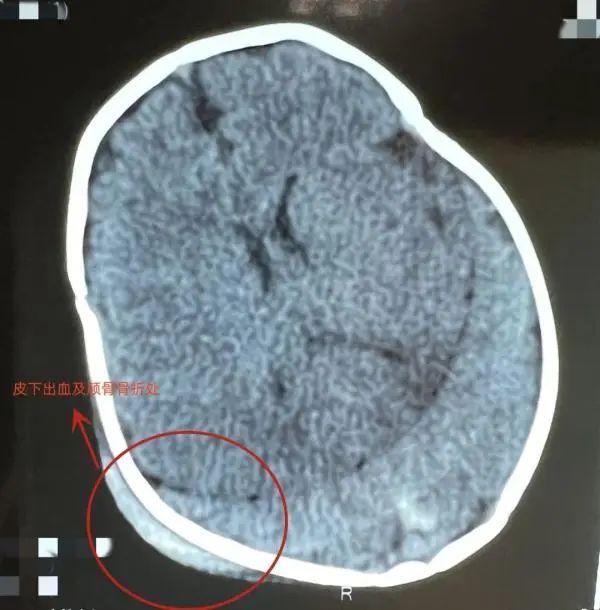

经过头部CT检查,发现皮下有出血,颅骨有凹陷骨折,颅内也有少量出血伴有脑挫伤。经过治疗,孩子病情平稳,出血没有继续增加。